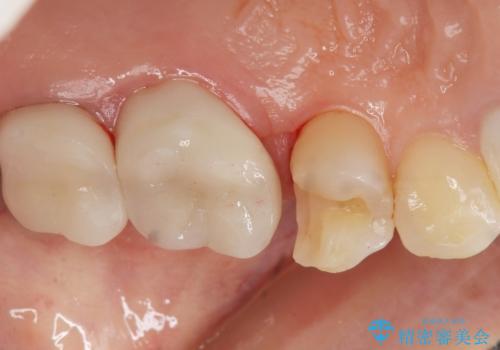

治療後はしみなくなり、違和感のない自然な咬み心地にご満足頂けました。

「割れる心配のないゴールドにしたいけれど、目立ってしまうかしら...」と心配されており、不要に歯質を削合しないよう注意を払い最小限の大きさのインレーを装着したところ、「あまり目立たなくて良かった!」とおっしゃって下さいました。